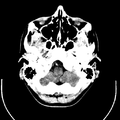

تصوير مقطعي حاسوبي

التصوير المَقْطَعي الحاسوبيX-ray computed tomography نظام تصوير بالأشعة السينية، يُسْتخدم لتصوير مختلف أجزاء الجسم مثل الرأس والقلب والبطن. ويستعين الأطباء بالتصوير المقطعي الحاسوبي على تشخيص الأمراض وعلاجها. وتسمى هذه التقنية أيضًا التصوير المقطعي المحوسب أو التصوير المقطعي المحوري المحوسب.

معرض الصور